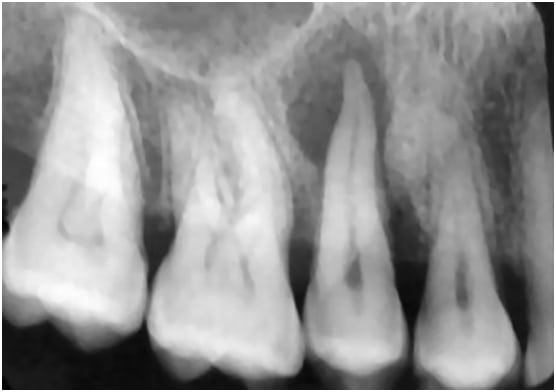

Periapical Pathology Identification

The Challenge

Patient presented with vague pain in lower right quadrant. Standard bitewings were inconclusive.

AI Finding

AI analysis of periapical radiograph highlighted a 3mm radiolucency at the apex of #30.